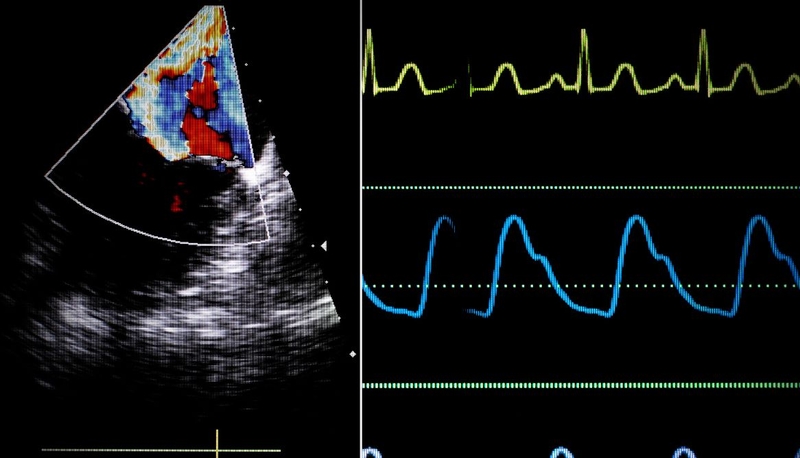

Hoạt động cơ học của tim chỉ có thể diễn ra khi được khởi phát và đồng bộ bởi hệ thống dẫn truyền điện học nội tại. Tâm điểm của hệ thống này là nút xoang – bộ tạo nhịp tự nhiên của tim, nằm ở thành nhĩ phải, khởi phát các xung động điện đều đặn. Xung điện từ nút xoang lan đến nút nhĩ thất – nơi làm chậm dẫn truyền để tạo thời gian nhĩ co bóp trước thất. Sau đó, xung động được truyền nhanh chóng qua bó His, nhánh phải – trái và mạng Purkinje, đảm bảo sự khử cực đồng thời của cả hai tâm thất. Hiện tượng khử cực lan tỏa và tái cực có trật tự giúp tim co bóp đồng bộ và hiệu quả, giữ cho chu trình tuần hoàn diễn ra liên tục.